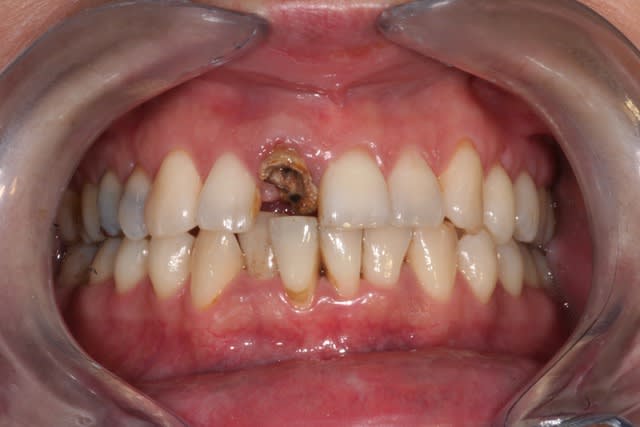

Dès que je peux, je réalise endo + prov + empr dans la séance, et si le cas s'y prête je réalise une RCR collée en profitant du fait que j'ai déjà isolé le champ opératoire:

Gain de temps, diminution du risque de contamination de l'endo pendant les interséances.

Je fais cela depuis déjà 6/7 ans et je m'en porte très bien.

Par contre j'obture avec la technique Macspadden et surtout plus avec des thermafill: c'est cher, c'est chiant à désobturer, je me sens pas de le faire dans la même séance.

2.préparation du logement canalaire au LARGO 2 (après réalisation de l'endo si nécessaire) et essayage du tenon qui doit être flottant pour e^tre ensuite entierement englobé dans la résine composite de reconstruction

3. nettoyage méticuleux des surfaces à coller : fraises LN, air abrasion et insert US type perio (N°60 sur Soniflex) à faible puissance avec irrigation abondante

4.réalisation de la reconstruction:

pour les tenons, je privilégie le tenon en fibre de verre pour la transmission de la lumière pour la photopolymérisation. Je prends les plus simple possible et les moins chers: GLASSIX pour les cylindriques et Advanced Dental Composite pour les cylindroconiques

Dans quelques rares cas, j'ai utilisé un CVIMAR en capsule pour sa facilité d'utilisation (pour des cas avec des parois importantes).

Sinon en général, j’utilise une résine DUALE (car même avec un tenon en fibre de verre je ne suis pas sûr de la transmission des rayons UV). Tu en trouves plein sur le marché, mais j'ai une préférence pour la PARACORE de chez COLTENE ou le CoreXflow de chez dentsply pour leur thyxotropie.